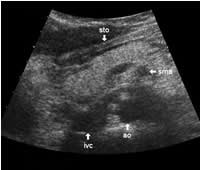

More or less fat tissue can be seen separating the pancreas from the following structures: The head and body of the pancreas are located below the liver, and below and generally behind the distal part of the stomach. The pancreatic head and body are located in front of the inferior vena cava and the aorta with the celiac trunk. To the far left, the tail of the pancreas has a position below the spleen and above the left kidney.

The following study describes anatomical landmarks in the ordinary pancreas of a thin patient:

Transverse planes in caudal direction: